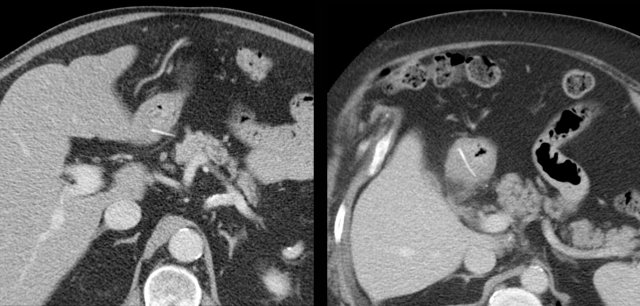

A 74-year old woman presents with deeply located, lower abdominal pain since 3 weeks. Lab: 15 leukocytes, CRP 150. She had multiple gynaecological operations in the past.

CT was done and revealed a bony foreign body, which, at both ends, appeared to perforate the sigmoid.

Endovaginal US confirmed that the foreign body traversed the sigmoid lumen, so colonoscopic removal was possible.

During the endoscopical procedure, the chicken bone had to be broken in two parts in order to be safely removed. Uneventful recovery with help of antibiotics.